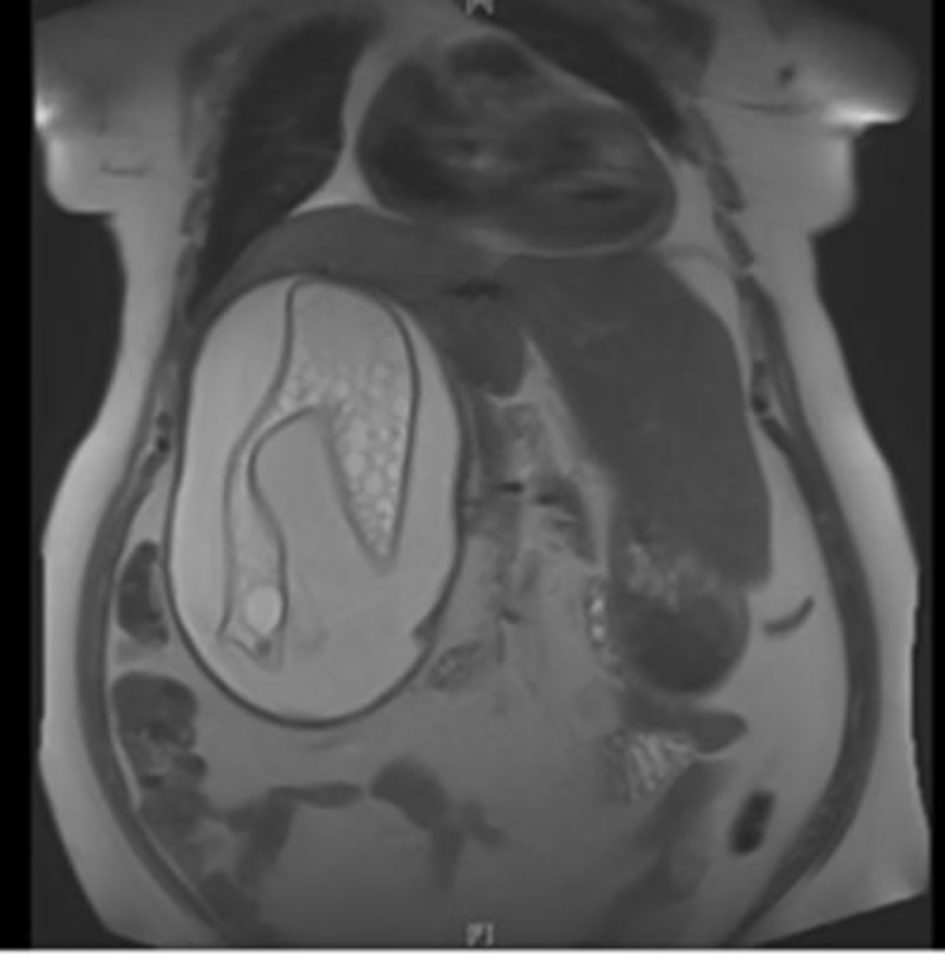

A 65-year-old woman with DM and hypertension was admitted to hospital with 8 years history of right lumbar pain. She used to live in the desert with strong history of contact with animals including dogs. She denied any urinary or other systemic symptoms. General examination was normal. Abdominal examination showed a 7 × 6 cm paraumbilical hernia. US abdomen showed a complex cystic structure measuring 20 × 9.4 cm occupying the right renal region that revealed multiple septations, coiled membranes and internal debris. Several internal small cysts are seen, features of which were consistent with hydatid cyst (Fig. 1, 2). Similarly, MRI disclosed a huge cystic lesion involving the upper and mid pole of the right kidney producing anterior displacement of the liver and pancreas with a thin T2 hypointense wall. There is a long smoothly outlined linear structure within the cyst, which includes multiple tiny cysts, likely representing an infolded ruptured wall of a hydatid cyst (Fig. 3). CT scan of the abdomen, chest and pelvis confirmed a giant hydatid cyst in the right kidney with no evidence of other cysts in the liver or the lungs (Fig. 4). The eosinophil count was normal both before and after surgery. Serum creatine remained normal despite a right kidney contributing only 5% of the renal function on DMSA scan. Urine and aspirate of cyst fluid was repeatedly negative for hydaturia. IHA serology for hydatid was also negative.

![]() Click for large image | Figure 3. MRI of the kidneys - a huge hydatid cyst with ruptured true wall in the right kidney. |